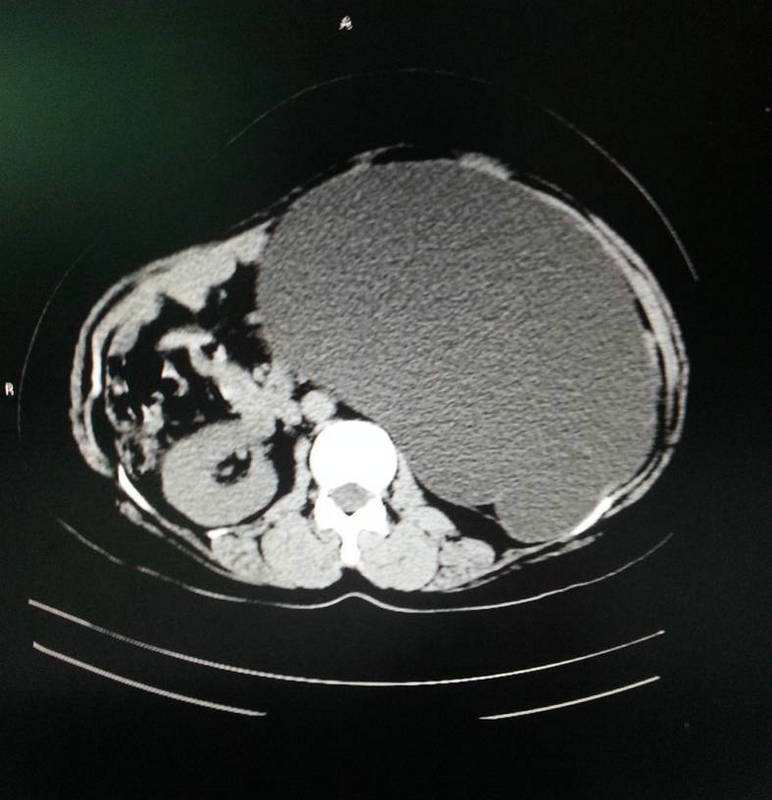

泌尿系统结石、前列腺增生症是我县常见病、多发病,2003年我院购进第一台进前列腺电切设备(德国产WOLF),由刘伟光副主任医师开展经尿道前列腺电切术、完成我院首例+前列腺增生微创手术,2009年泌尿外科成立之际在广州医学院微创中心袁坚主任指导下,先后开展经皮肾穿刺取石手术。科室先后派出多名医生到中山大学附属二院、广州医学院微创中心、中山市人医进修泌尿系结石微创治疗技术。自2010年医院再次投入科室购进进口输尿管镜、小儿输尿管镜、输尿管肾镜、经皮肾镜(德国的WOLF),全面开展肾、输尿管结石微创治疗手术,由于微创技术的开展,显著提高了泌尿系统结石、前列腺增生症手术治疗效果,获得了良好的社会效益。使科室处理泌尿系结石、前列腺疾病能力处于区域领先水平,科室近2年内逐步在该专业组开展泌尿系疾病腹腔镜治疗手术,成功开展腹腔镜下肾切除术、肾囊肿去顶、精索静脉曲张高位结扎手术,新技术的应用不仅使该专业组成为科室优势专业,也为我县常见病、多发病的有效治疗做出了贡献。

泌尿外科其他疾病、肿瘤专业组主要负责泌尿肿瘤、创伤、先天畸形等泌尿疾病的外科治疗。2009年开科以后先后开展外伤性肾切除、修补术,肾肿瘤根治切除术、膀胱部分切除与全切术,2010年后先后在中山医附属二院支持下开展了膀胱癌电切,肿瘤术后化疗,输尿管狭窄微创治疗技术,肾输尿管结合部狭窄整形手术。成为科室传统开放与微创手术结合密切的专业组,取得良好手术效果,推动了科室业务开张,现非结石手术每年约开展100台次,有力拓宽了科室专科治疗疾病范围。